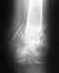

Re: Ложный сустав или новый перелом?

К сожалению (но, не к Вашему унынию!) все так и есть... Ведь почему сломался гвоздь? Нижний перелом не сросся, отломки двигаются, что приводит к усталостному слому металлического гвоздя! Ведь если пару десяток раз перекручивать - перегибать металлическую прoволоку - она сломается. Тоже самое и с любой конструкцией, только не десяток раз, а несколько тысяч, а Вы за 10 месяцев успели пройти опасный цикл...